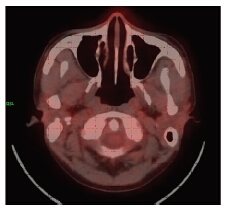

1 病例资料患者,男,22岁,因“左侧鼻塞2月”于2013年7月就诊,无发热、盗汗、体重减轻。血常规、凝血功能、乳酸脱氢酶(LDH)均正常,EBV-DNA 1.05×105/L。CT示:左侧鼻腔内见团块状软密度组织影,左侧下鼻甲部分骨质被破坏,左侧上颌窦内见密度增高影,窦壁骨质结构未见明显异常,左侧上颌窦少许炎症,见图 1。彩超示:双侧颈部、锁骨上下区、腋窝、腹股沟、肝、胆、胰、脾、腹主动脉及下腔静脉旁淋巴结均未见异常。骨髓细胞学检查未见异常。行左侧鼻腔肿物切除术,病理示:(左侧鼻腔)非霍奇金淋巴瘤,免疫组织化学:CD2(+),CD56(+),Granzyme-B(+),CD3(+),CD20(-),Ki-67(+60%),EBER(+),符合结外NK/T细胞淋巴瘤,鼻型,见图 2。诊断:结外NK/T细胞淋巴瘤,鼻型,ⅠA期,IPI评分0分。给予地塞米松+异环磷酰胺+顺铂+依托泊苷+门冬酰胺酶(DICE+L-asp)方案化疗6个疗程。化疗后行PET-CT检查完全缓解,见图 3。6个疗程化疗后第7天出现持续发热,最高39.5℃,无寒战、伴咳嗽、腹胀、腹痛、便血。查体:中度贫血貌,全身皮肤黏膜中度黄染,无皮下出血。口腔黏膜完整,咽充血、水肿、双侧扁桃体无肿大。颈后三角区可触及一2 cm×2 cm肿大淋巴结,质韧、无压痛、固定,余浅表淋巴结未触及肿大。心肺听诊无异常。腹部轻度肿胀,右下腹轻压痛,无反跳痛。肝脏肋缘下3 cm,质中,无压痛。脾肿大,肋缘下3 cm。双下肢轻度水肿。辅助检查:D-二聚体 2.0 mg/L,纤维蛋白原0.26 g/L;血常规: WBC 0.98×109/L,HB 21 g/L,PLT 11×109/L,淋巴细胞 0.56×109/L。肝功能:总胆红素103.7 μmol/L,直接胆红素93.7 μmol/L,间接胆红素10.0 μmol/L,谷丙转氨酶 93 u/L,谷草转氨酶524 u/L,白蛋白27.5 g/L,β2微球蛋白3.78 mg/L。EBV-DNA 3.02×105/L;CMV-DNA(-)。铁蛋白2 000 μg/L。外周血象:淋巴细胞占58%,异型淋巴细胞占34%,见图 4。骨髓象:淋巴细胞占7.5%,其中异型淋巴细胞占3%,见图 5。综合考虑诊断为鼻腔NK/T细胞淋巴瘤合并IM,给予更昔洛韦、阿糖腺苷抗病毒治疗,同时给予抗感染、保肝、输血等对症支持治疗,患者病情好转,症状体征消失,血象与肝功能等实验室检查正常。现已临床随访半年,病情稳定。

| 图 3 鼻腔NK/T细胞淋巴瘤治疗后并发传染性单核细胞增多症患者鼻咽18F-FDG PET-CT影像学表现 Figure 3 Nasopharyngeal 18F-FDG PET-CT imaging of patient with nasal NK/T cell lymphoma complicating infectious mononucleosis after chemotherapy |